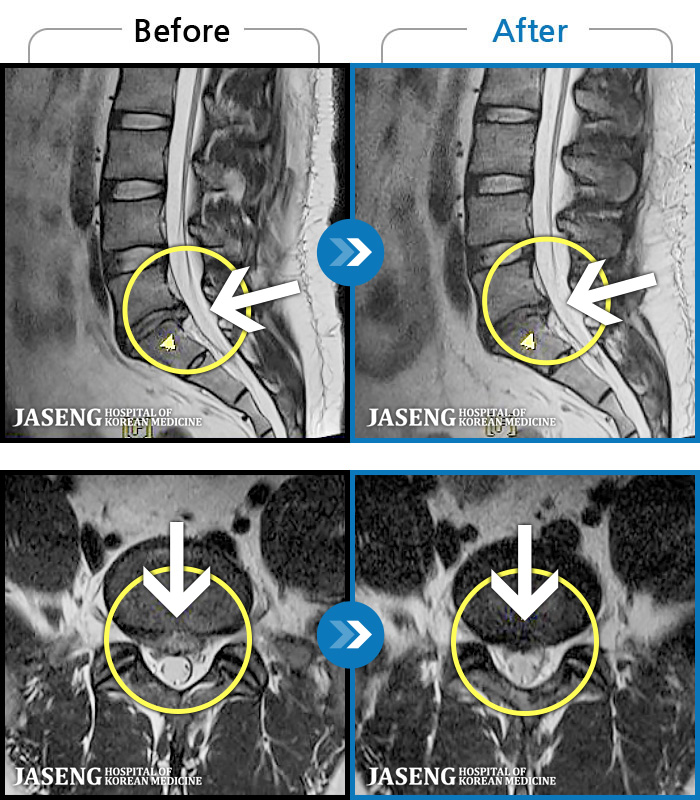

- MRI ġ

MRI ġ

1,293 MRI ũ ʸ Ȯϼ.